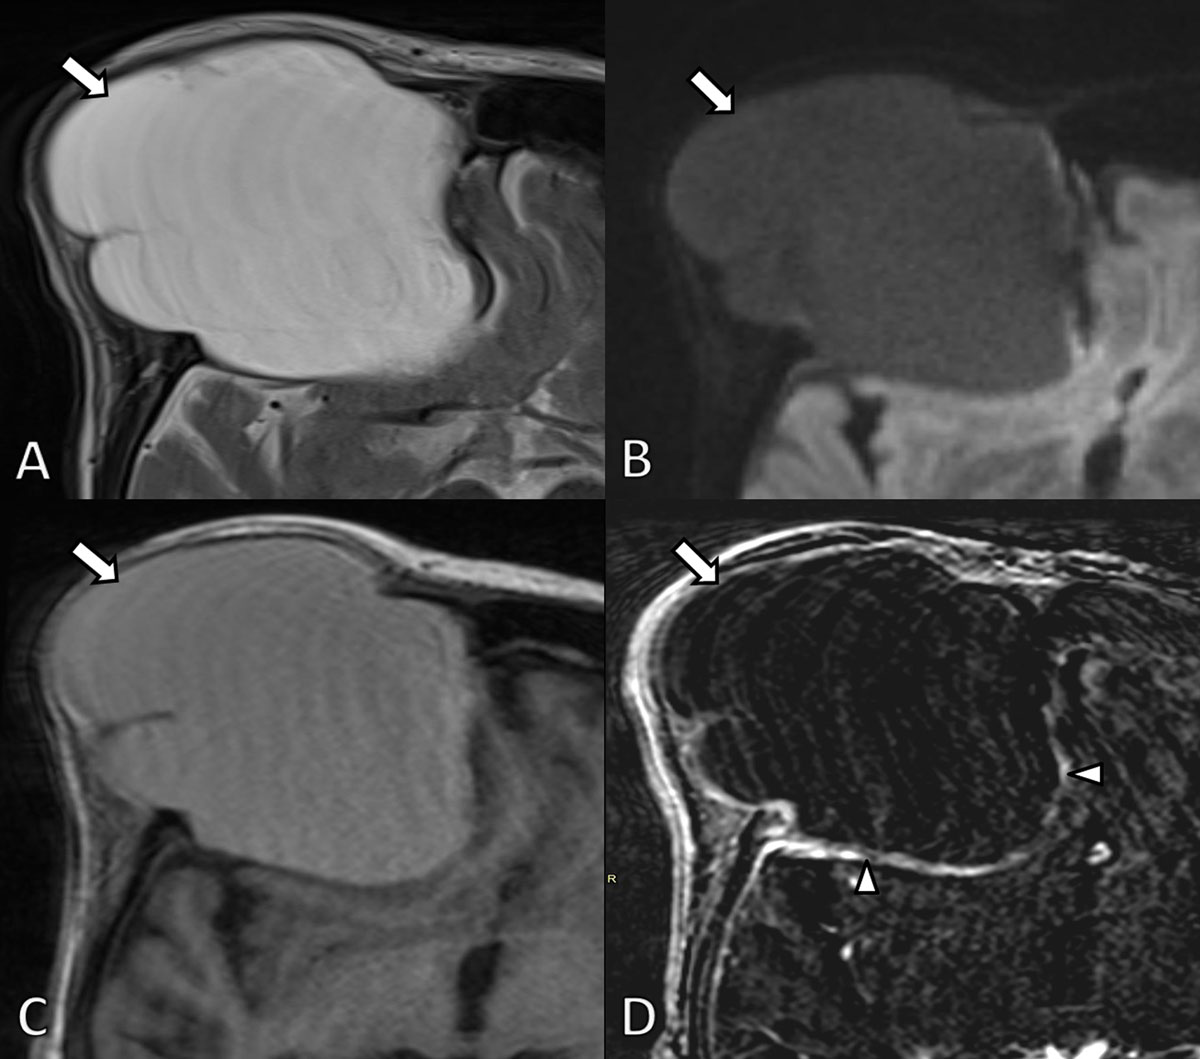

Subsequent MRI of the brain (Figure 2) depicted a well-defined expansile mass being slightly hyperintense on T1-weighted images (WI) and markedly hyperintense on T2-WI. A neurosurgical consult was planned but the patient did not show up. The patient was readmitted four years later because of recurrent falls and memory loss. Repeated CT (Figure 3) and MRI (Figure 4) demonstrated progressive expansion of the mass with increased destruction of the frontal bone. Based on the location at the frontal sinus and the imaging features, a presumptive diagnosis of a giant frontal mucocele was made, which was confirmed upon neurosurgical resection.

Figure 4

MRI scan 4 years later. A. Axial T2-WI. B. Diffusion weighted image (b1000) and C T1-WI and D. subtraction image of T1-WI before and after gadolinium contrast administration. The lesion (arrows) is slightly more hyperintense on T2-WI and slightly less intense on T1-WI compared to the previous examination due to a higher fluid content. There is no diffusion restriction and persistent subtle peripheral contrast enhancement (arrowheads).